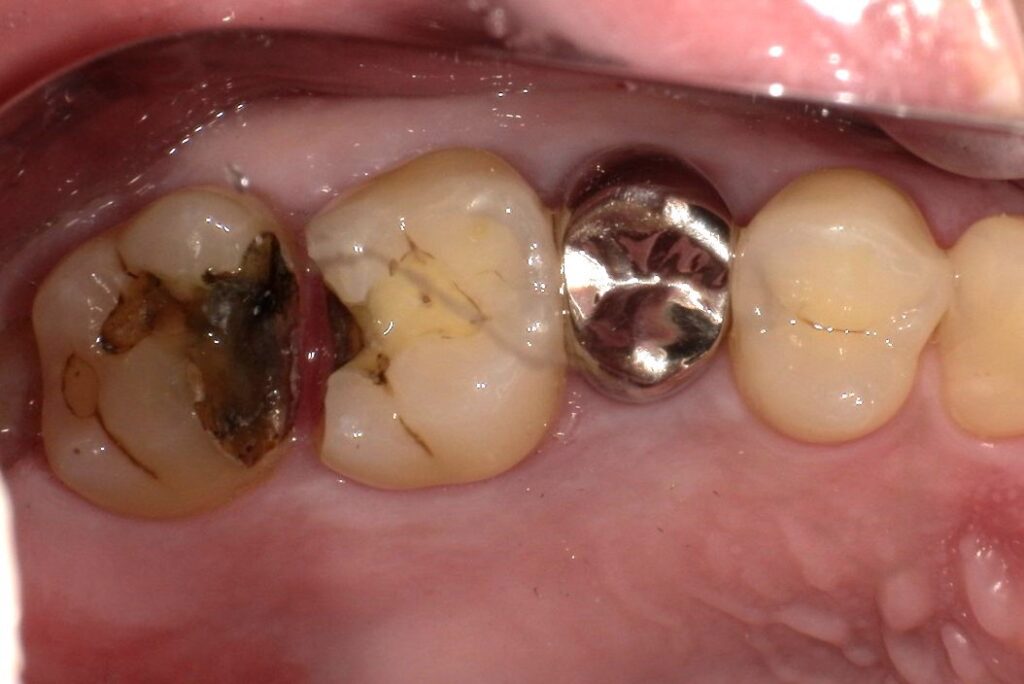

Case.02

治療前

治療後

| 主訴 | むし歯で歯が欠けてしまった。 |

| 治療期間 | 約6ヶ月 |

| 治療費 | 約¥100,000(被せ物代別) |

| 治療内容 | むし歯により抜歯となった部位(右上奥歯)に親知らずを移植。 |

| 治療のリスク | 移植歯がうまく定着しない可能性があります。また、長期的には△。 |